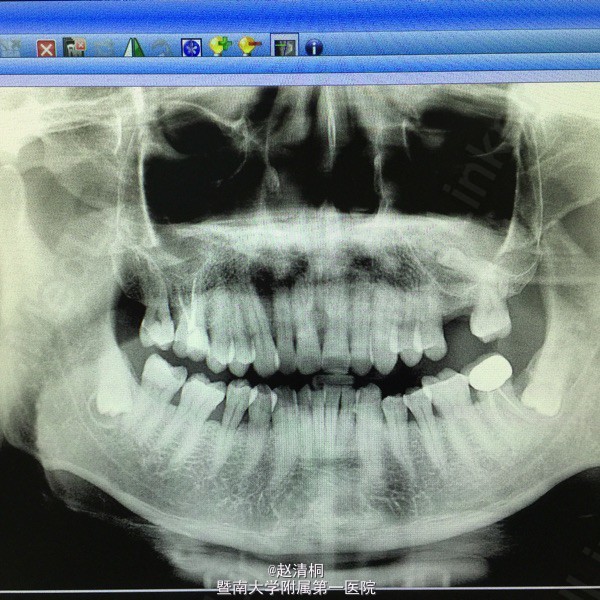

CBCT显示只有3mm骨量,上颌窦内侧壁有一多生牙,没有CT,这种病例不敢种的。